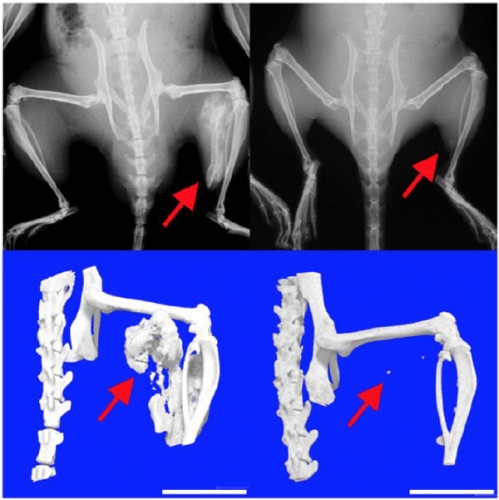

京都大学iPS細胞研究所の戸口田淳也教授らのグループは1日、筋肉や腱などが骨に変化してしまう難病、進行性骨化性線維異形成症(FOP)の治療薬候補を定めたと発表。iPS細胞を用いた研究の末、効果のある薬を特定した。iPS細胞応用による新薬誕生に向けた日本で初めてとなる治験は、近く実施される見込みだ。

身体中のほぼ全ての細胞になれるiPS細胞は、難病患者から提供された細胞を基にしてその病態を再現できる。FOP患者由来のiPS細胞により、病態メカニズムの解析は進んでいた。今回、その細胞への約7,000もの物質投与を経て、ラパマイシンという薬を選び出した。

FOPは、全身の筋肉や腱、靭帯などが徐々に骨へと変化していく進行性の病気で、発症の割合は200万人に1人、患者は日本全国に約80名存在する。ラパマイシンにはその骨への変化を抑える効果があると、研究で判明した。